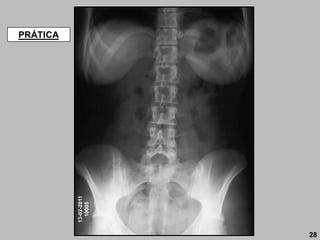

ABDOME

Básica:

• AP DECÚBITO DORSAL.

Especiais:

• PA DECÚBITO VENTRAL;

• DECÚBITO LATERAL (ESQUERDO);

• AP ORTOSTÁTICO;

• DECÚBITO DORSAL (lateral direito);

• LATERAL.

59

60

MARCOS TOPOGRÁFICOS

1-Ponta do processo

xifóide (nível de T9-T10).

2- Margem costal inferior

(nível de L2-L3).

3- Crista ilíaca (nível de

L4-L5).

4- Espinha ilíaca ântero-

superior (EIAS).

5- Trocânter maior.

6- Sínfise púbica.

7- Tuberosidades

isquiáticas.

São sete (07) os marcos topográficos para posicionamento do abdome ou

para localização de órgãos.

T9-T10

L2-L3

L4-L5

1.00 DfoFi RC:  a crista ilíaca

AP DECÚBITO DORSAL

Básica

61